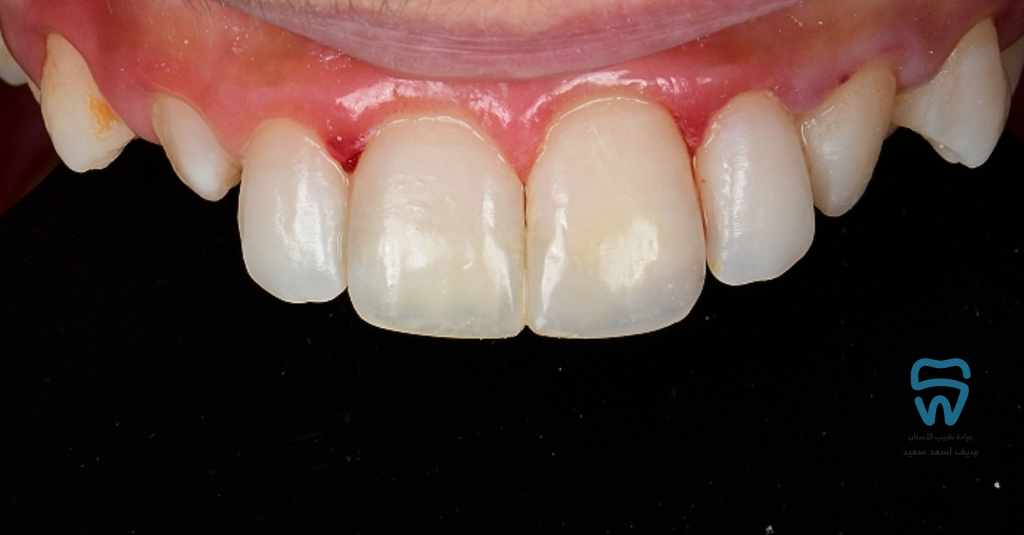

patient came with 2 fractured upper centrals

closer look at the condition

Complicated crown fracture